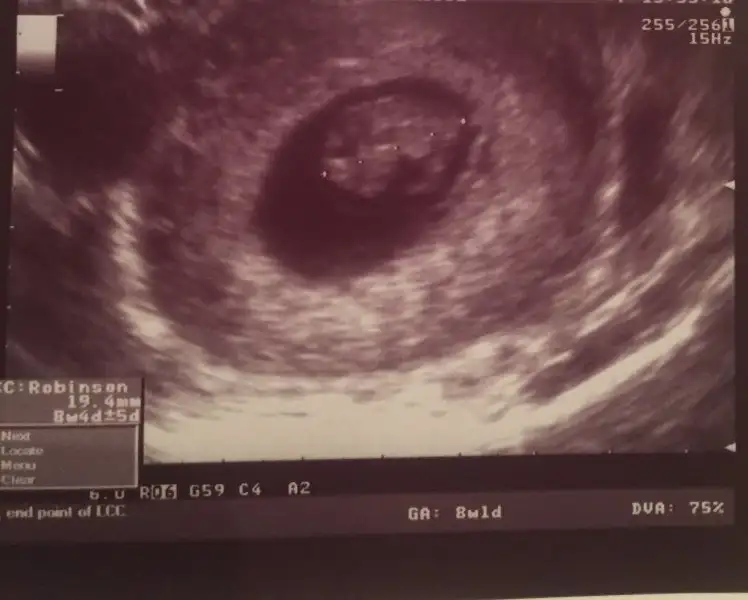

ah bılmez mıyım herkes cok bılıyo ztn kız olsa nıye erkek yok erkek olsa kızda olsaydı deyip moralını bozuyolar ınsanın. ikiside evlat hıcbır farkı yok saglıklı hayırlı olsun yeterkı.inşallah gönlünden geçen olur. sen yınede kulak asma kımseye Allah en hayırlısını nasip etsin ama bnm ultrason resmım senınkının tam tersı yanı bbek sagdaydı dun doktor kıza benzıyor dedı tabı bnmde kesn degılde kısmet artık hakkımızda hayırlısıKarından ıltrason inaşşaah karfeşim öyledir 3 tane prensesten sonra sağlıklı bir erkek olur. Ben ve eşim sıkıntı hiç bir zaman yapmadık ama toplum devamlı imalı laf sokmalarından sıkıldım .

Teşekkür ederim canım benim. Allahta senin gönlünde ne varsa onu hayırlısıyla versin . Hele hiç çocuğu olmayanlara taddırsım Anneliğiah bılmez mıyım herkes cok bılıyo ztn kız olsa nıye erkek yok erkek olsa kızda olsaydı deyip moralını bozuyolar ınsanın. ikiside evlat hıcbır farkı yok saglıklı hayırlı olsun yeterkı.inşallah gönlünden geçen olur. sen yınede kulak asma kımseye Allah en hayırlısını nasip etsin ama bnm ultrason resmım senınkının tam tersı yanı bbek sagdaydı dun doktor kıza benzıyor dedı tabı bnmde kesn degılde kısmet artık hakkımızda hayırlısı

buna gore erkek canım. benım karından boyleydı doktor kıza benzıyor dedı. kesındegıl benımkıde ama kesnlesırse teorı bnde tuttuEki Görüntüle 1939188 Eki Görüntüle 1939187 Kizlar banada baksanizaa altan utrasyon yani vajenden